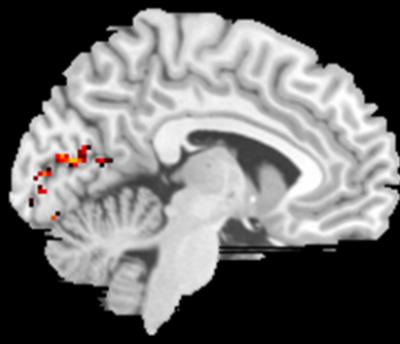

The researchers presented 13 volunteers with a series of tests designed to visually stimulate their peripheral regions and measure brain activity with functional magnetic resonance imaging. They found that when patients visually stimulated the preferred retinal locations, they increased brain activity in the same parts of the visual cortex that are normally activated when healthy patients focused on objects in their central visual field. They concluded that the brain had reorganized itself.

The parts of the visual cortex that process information from the central visual field in patients with normal vision were reprogrammed to process information from other parts of the eye, parts that macular degeneration patients use instead of their central visual areas.